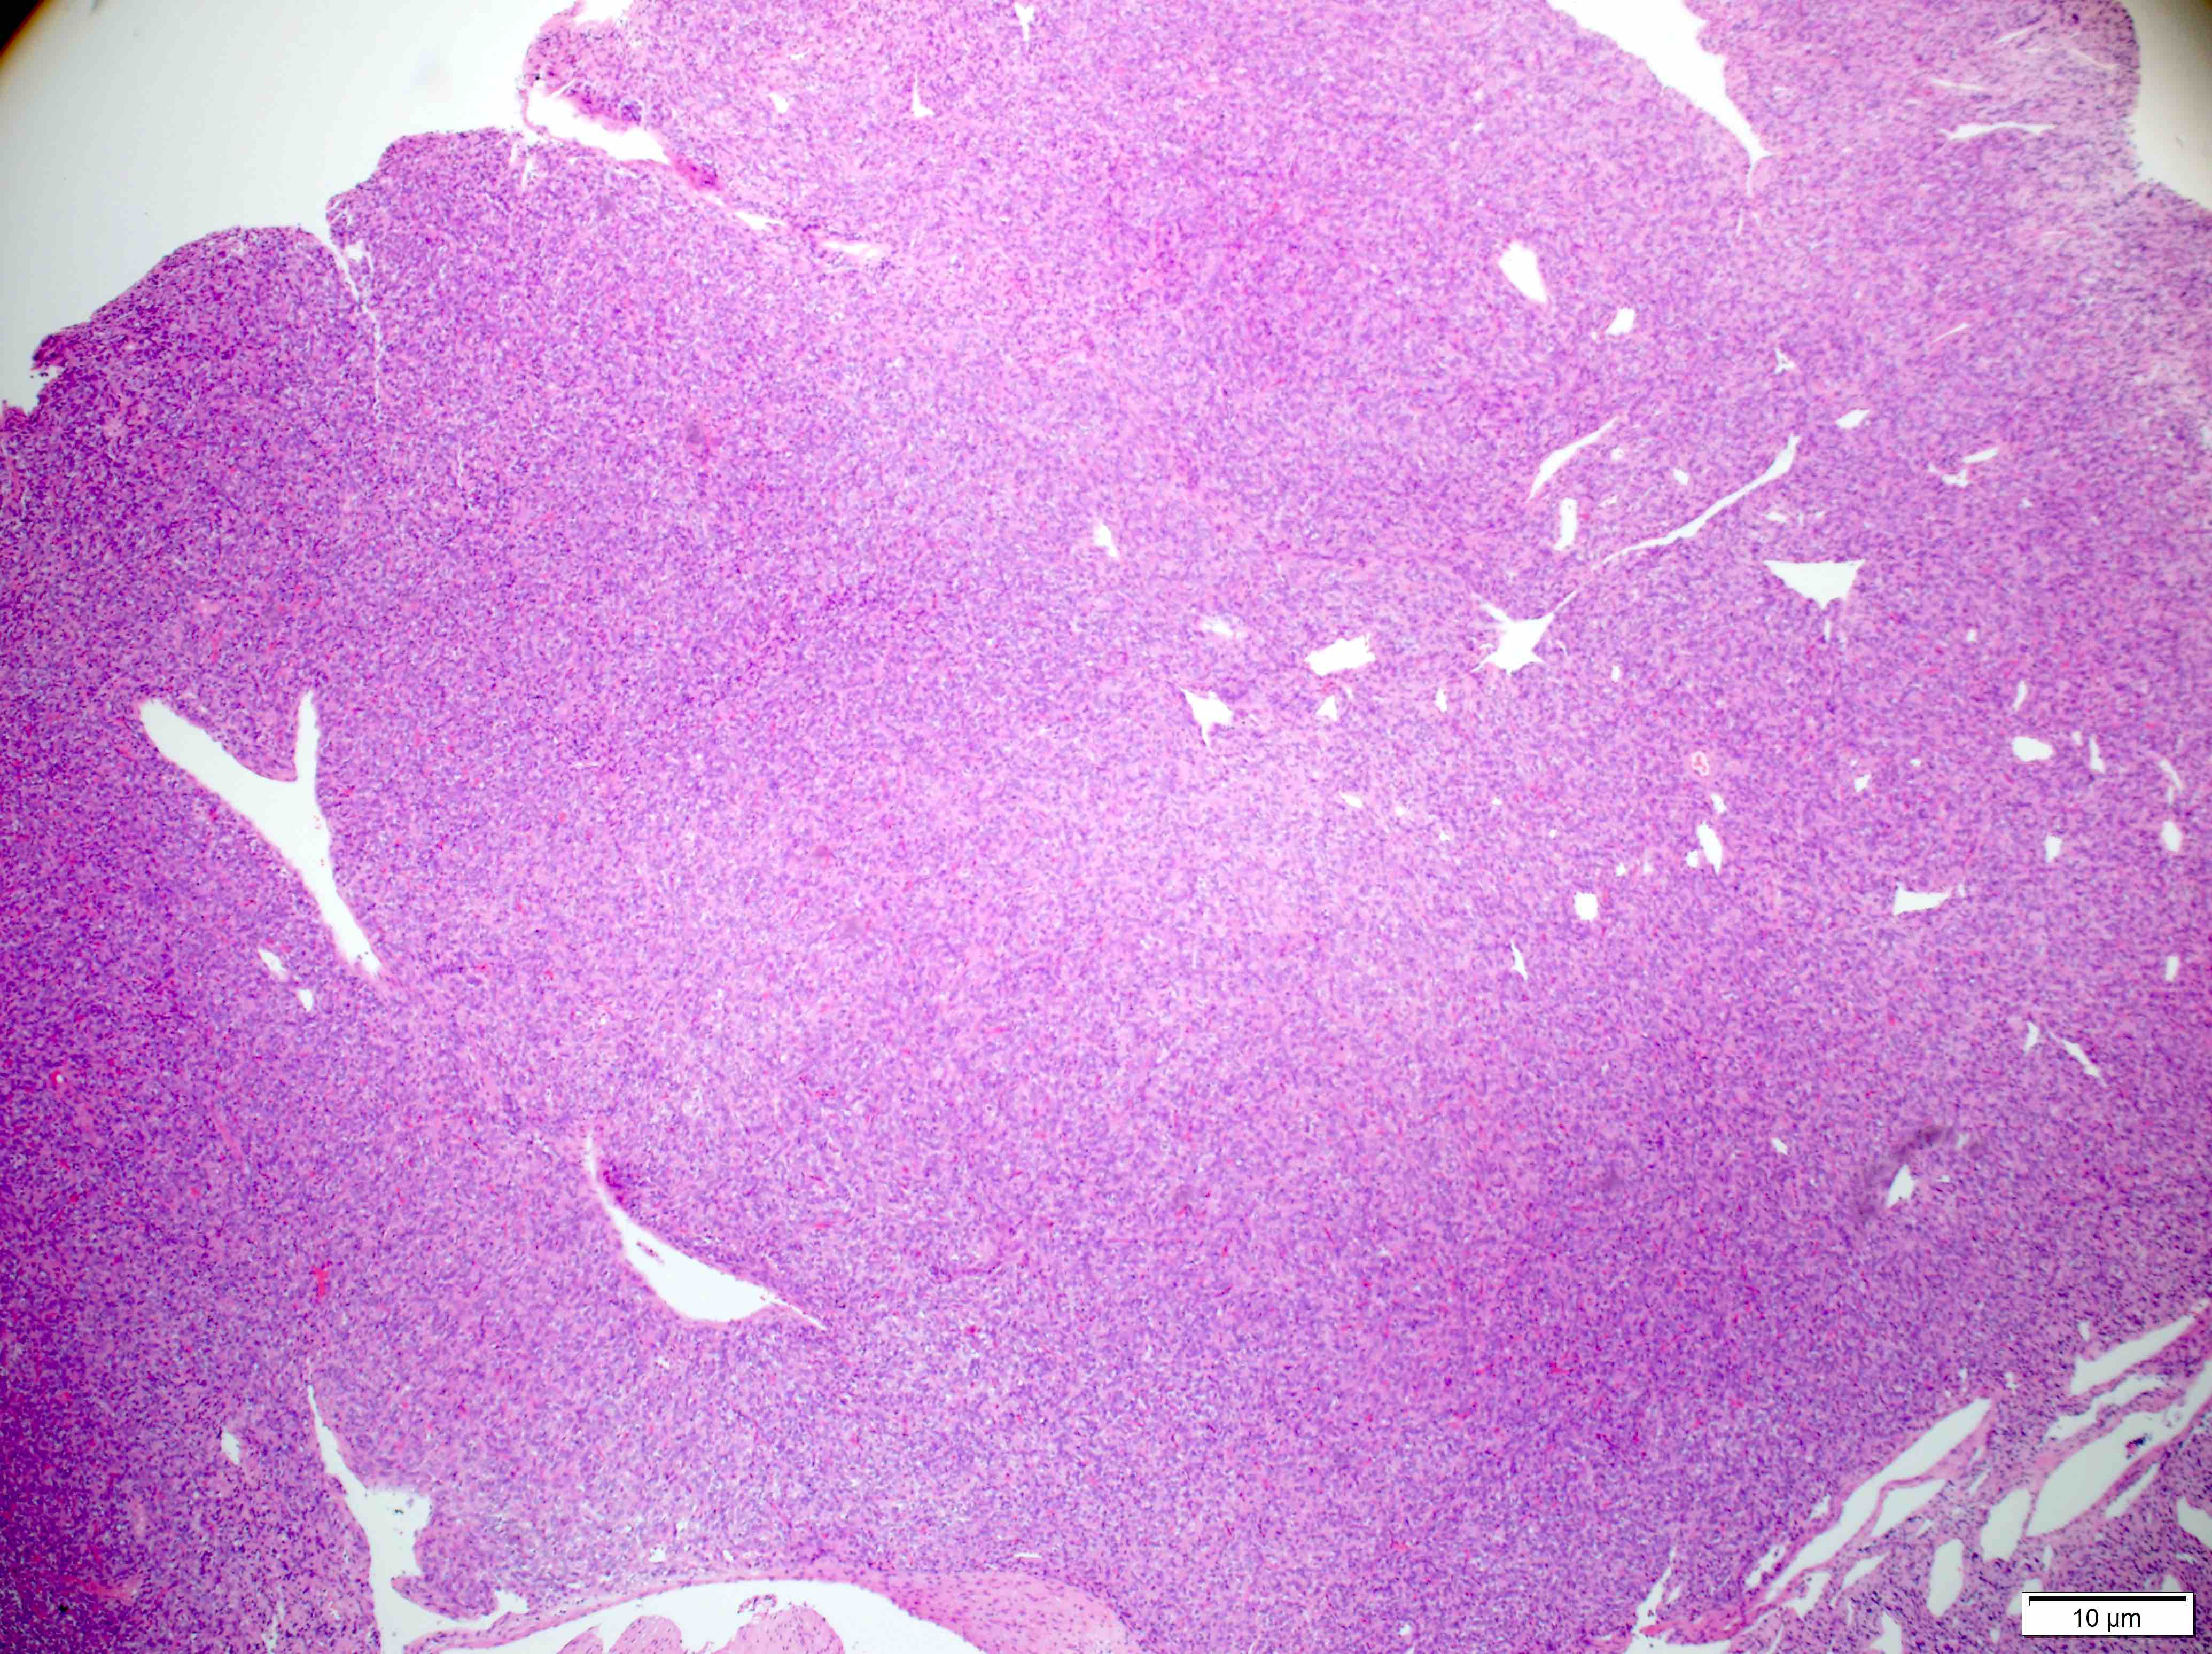

Microscopic (histologic) description

- Essential: patternless pattern of spindle cells, often solid but can also have papillary and other architectures, arranged around branching hyalinized vessels

- Varying amounts of stromal collagen and overall cellularity

- Nuclei are bland, without features seen in mimicking neoplasms

- WHO grading criteria:

- < 5 mitoses/10 high power fields (HPF) = grade 1

- ≥ 5 mitoses/10 HPF = grade 2

- ≥ 5 mitoses/10 HPF with necrosis = grade 3

- Often has staghorn vasculature

Microscopic (histologic) images